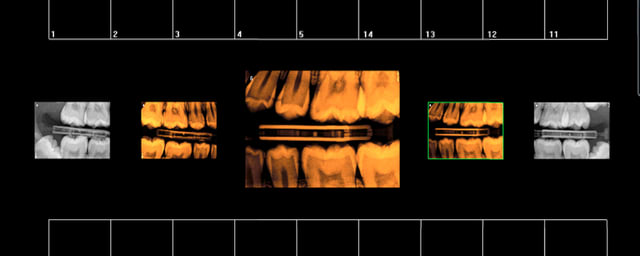

HBQK 046 ( 9 radios)

12 17 21 23 26 32 41 43 47

Diagnostic : RAS

Orientation thérapeutique : à surveiller régulièrement.